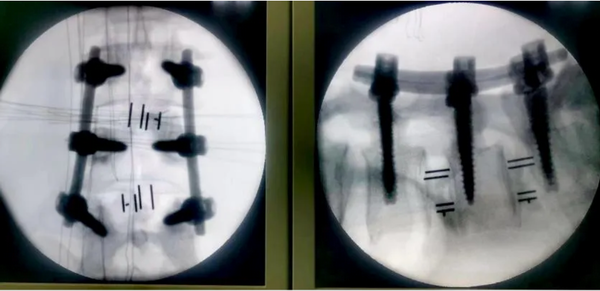

楊峻主任團(tuán)隊(duì)術(shù)中利用3D打印模型和導(dǎo)板輔助,精準(zhǔn)、高效進(jìn)行手術(shù)。

在3D數(shù)字打印技術(shù)輔助下手術(shù)順利完成,術(shù)中影像可見:精準(zhǔn)置釘,徹底減壓,充分植骨融合,退變側(cè)凸滑脫獲得矯正。術(shù)后,患者多年的腰腿疼麻癥狀明顯緩解,對手術(shù)效果滿意。不久,患者將更好的回歸日常生活和生產(chǎn)。